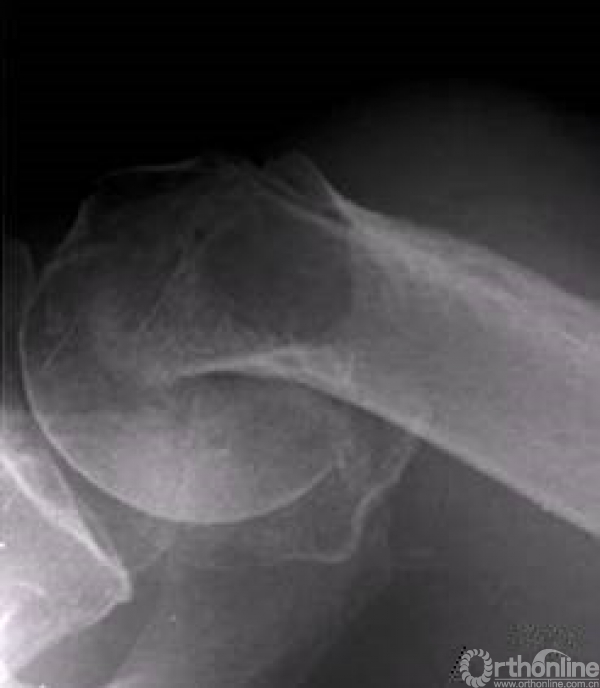

肱骨近端骨折十分常见,我们临床中最常用的入路为胸大肌-三角肌入路。

大结节向后侧移位较大,所以外侧劈三角肌入路,逐渐得到了大家的认可,该入路需要注意几个问题。

病例1

4部分骨折